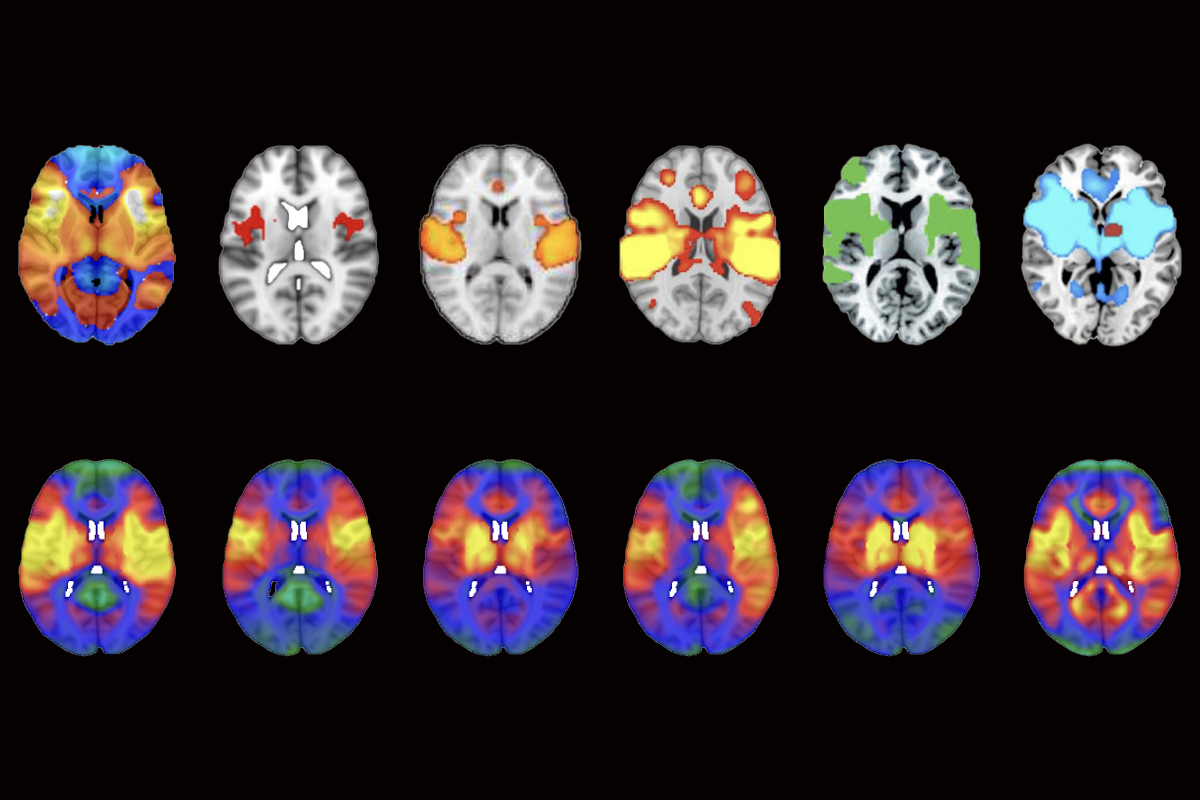

But networks identified using LNM are, for the most part, not rooted in a condition’s biology, according to the new study. Instead, a mathematical flaw in the method causes the approach to produce a nearly identical network map for any given dataset, the new study suggests.

Van den Heuvel pored over other papers on LNM and repeatedly turned up the same map: The networks altered in psychosis and smoking addiction were also altered in post-traumatic stress disorder, migraine, insomnia, vertigo, and so on. All of these conditions show activation of the insular cortex, anterior cingulate cortex and the frontal cortex, he found.

But each new network added to a lesion network map derives primarily from the original typical connectome, van den Heuvel and his colleagues found. That means that with each new participant and lesion, an LNM map increasingly recapitulates basic properties of the typical connectome; disorder-specific contributions to the map are minimal.

When van den Heuvel’s team applied LNM to a set of hypothetical lesions in randomized locations across the brain, the method produced essentially the same map.